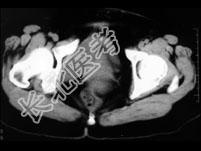

- 单项选择题女,32岁, 因停经46天,少许不规则阴道流血15天, 下腹胀痛3天入院,后穹窿穿刺抽出不凝血, CT检查如图所示,下列说法错误的是 ( )

A、在左附件区可见一椭圆形略高密度病灶

B、病灶外缘较光整

C、盆腔内较高密度积液

D、考虑为宫外孕

E、考虑为卵巢巧克力囊肿